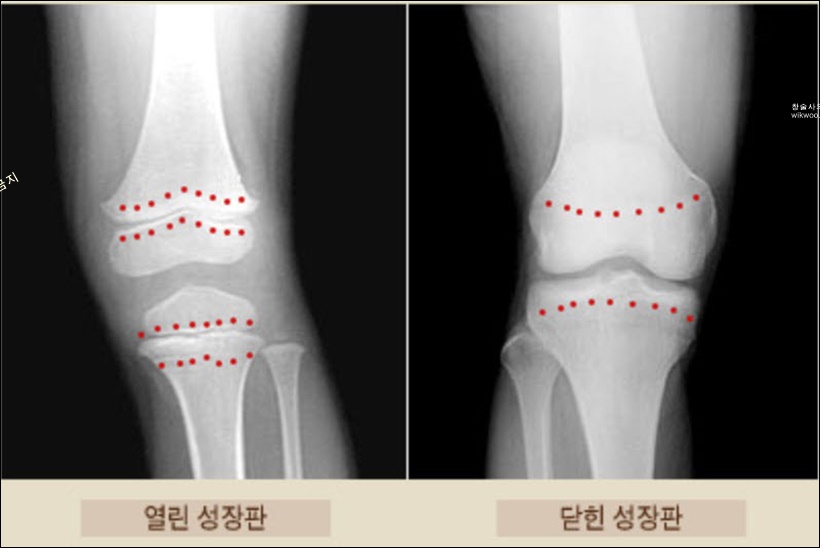

사람이 키가 자랄 수 있는 이유는 뼈가 자라기 때문입니다. 어린이의 손가락뼈, 다리뼈, 팔뼈 끝부분는 뼈를 만드는 세포가 있는데 이를 성장판이라고 합니다.

성장판이 닫힌다는 말은 뼈길이가 더이상 자라지 않는다는 것을 뜻합니다. 따라서 성장판이 닫히는 시기를 미리 알고 준비해야 자녀의 키가 더 커질 수 있습니다.